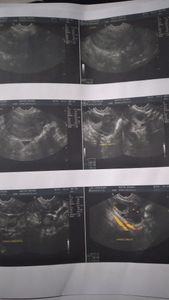

Olá pessoal tudo bem sou Edneia maffei e portadora de endometriose profunda e varises uterina Eu sofre da doença há 2 anos, mas o diagnóstico da emdrometriose saiu este ano

, quando surgiram novos sintomas, bem piores do que eu tinha. O caso é bastante delicado devido à progressão da doença. As lesões acometem diversas áreas, como atrás do útero, reto, intestino, vagina e principalmente os rim e ovários. Eu também tenho aderências e tudo isso levou a dor pélvica crônica, fazendo-a sofrer todos os dias com dores insuportáveis, o que muitas vezes tenho que ir ao pronto-socorro para tomar remédios fortes na veia. E ainda por cima, a endometrioma que eu tem no ovário direito tem 11 centímetros e vai precisar ser retirado, pois corre o risco de estourar e causar infecções! Estamos tentando fazer a cirurgia pelo SUS, mas o processo é demorado. Quanto mais o tempo passa, mais a doença progride e piora. Confesso que criei muita resistência antes de criar essa vaquinha, mas me vejo num beco sem saída. Eu trabalho de pintora residencial tem dias que não consigo ném trabalha Além da cirurgia,eu preciso desse dinheiro para o pré e pós-operatório, gastos com (cirurgia), medicamentos e tratamento de manutenção clínica, que é feito com vários profissionais. Se sentir vontade de me ajudar, saiba que você fará parte de uma grande mudança na vida de alguém!